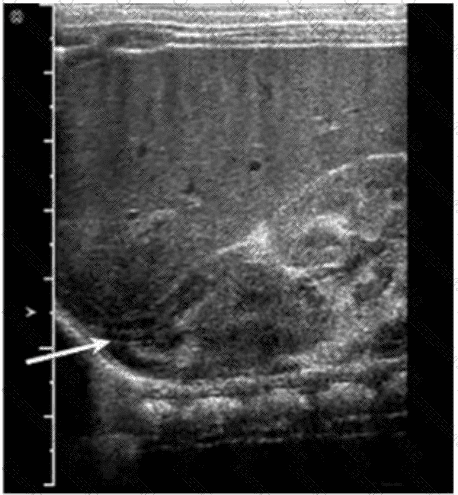

Questions 28

Which condition is most consistent with the findings in this image?

AB-Abdomen Question 28

Options:

A.

Fungal balls

B.

Renal cell carcinoma

C.

Acute pyelonephritis

D.

Medullary sponge kidney

Buy Now